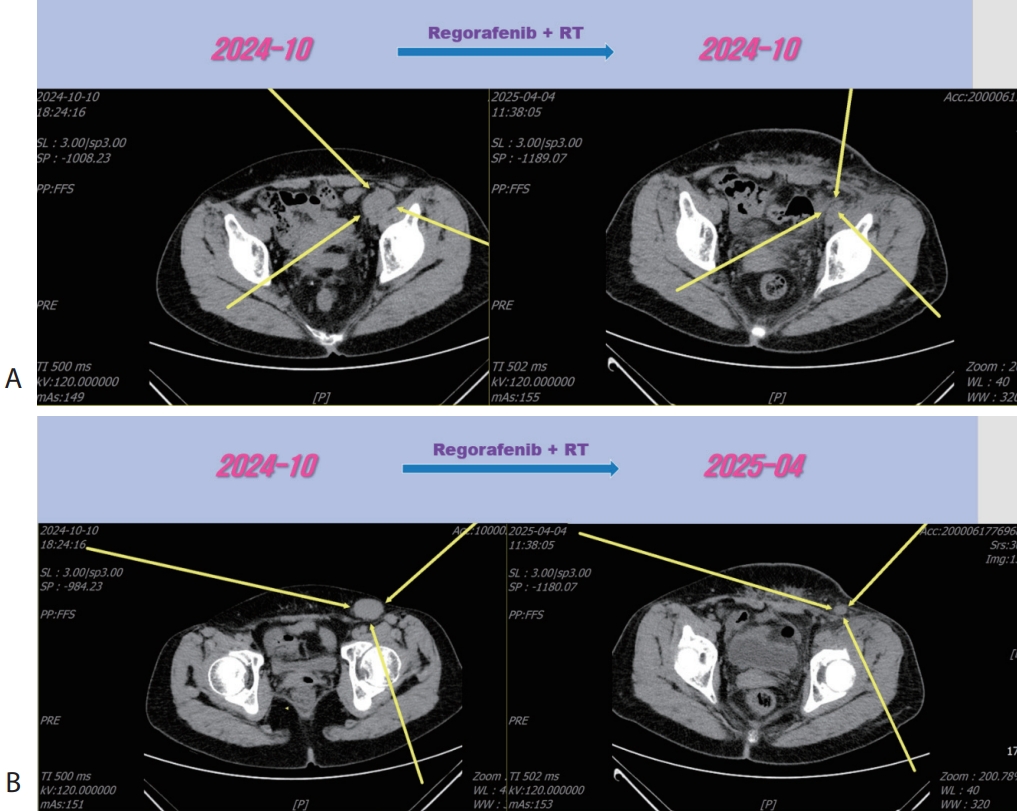

Figure 1.Liver CT scan. Huge portocaval lymph node (6 cm sized) metastasis was observed. CT, computed tomography.

A 56-year-old woman with a multiple peritoneal and LN metastasis of HCC was admitted to our hospital from a nearby cancer center in November 2021. She already received right hemi-hepatectomy for initial HCC in 2018 and radiofrequency ablation for recurred tumor in 2019 and multiple times of excision for peritoneal & LN metastasis in 2021. However the metastasis was aggravated despite of previous several times of metastasectomy. Computed tomography (CT) revealed multiple LN & peritoneal metastasis (maximum diameter 6 cm) (